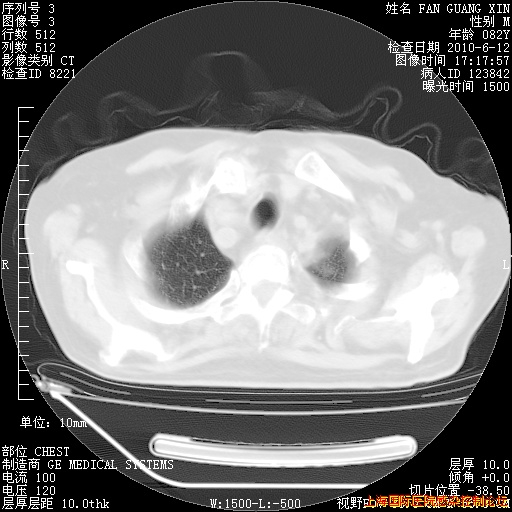

补发6月12日肺部CT肺窗

6月12日肺窗

整整相隔30天的肺部CT好像有所好转啊。甲强龙减量第3天,需要观察体温。